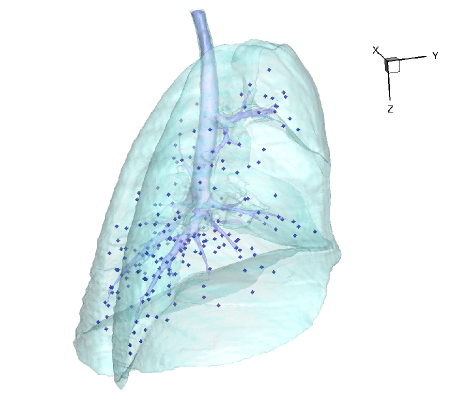

For each animal, approximately 200 automatically identified landmarks within the lungs are used to compute registration accuracy. The landmarks are widely distributed throughout the lung regions. Figure 5 shows an example of the distribution of the landmarks in animal D for both the and images. The coordinate of each landmark location is recorded for each image data set before and after registration for all four animals. Figure 6 shows the landmark distance before and after registration for four animals. The grey boxes show the magnitude of respiratory motion during the tidal breathing. For all four animals, before registration, the average landmark distance is 6.6 mm with a minimum distance of 1.0 mm, maximum distance of 14.6 mm, and standard deviation of 2.42 mm. After registration, the average landmark distance is 0.4 mm with a minimum distance of 0.1 mm, a maximum distance of 1.6 mm, and a standard deviation 0.29 mm. The trends for all animals are consistent and the results demonstrate that the registrations produced good anatomic correspondences. All registrations were examined and it was confirmed that all Jacobian values had positive values.

Figure 5(a) shows the location of the (Xe-CT) slab overlaid on the image. Figure 7 shows an example of the image registration result from the image to the image. The first row shows the misalignment between the images before image registration. Though the images were acquired without moving the animal between the scans, there is still non-rigid deformation between scans as shown in Fig 7(d), as the black and white regions represent the large intensity difference between Fig. 7(a) and (b). In addition, the slice thicknesses were quite different which causes partial volume artifacts. After image registration, the image is aligned to the image, and the resulting difference image (shown in Fig. 7(e)) is near zero. The transformation from the to the image allows us to map the Xe-CT sV into the coordinate system of image. Note that since the regions outside the lung are not included in the registration process, the mediastinum and other body tissues are not aligned. Also note that the dorsal region of the lung shows a intensity difference after registration. This is due mainly to the gradual progression of atelectasis and tissue edema during the course of the experiment.